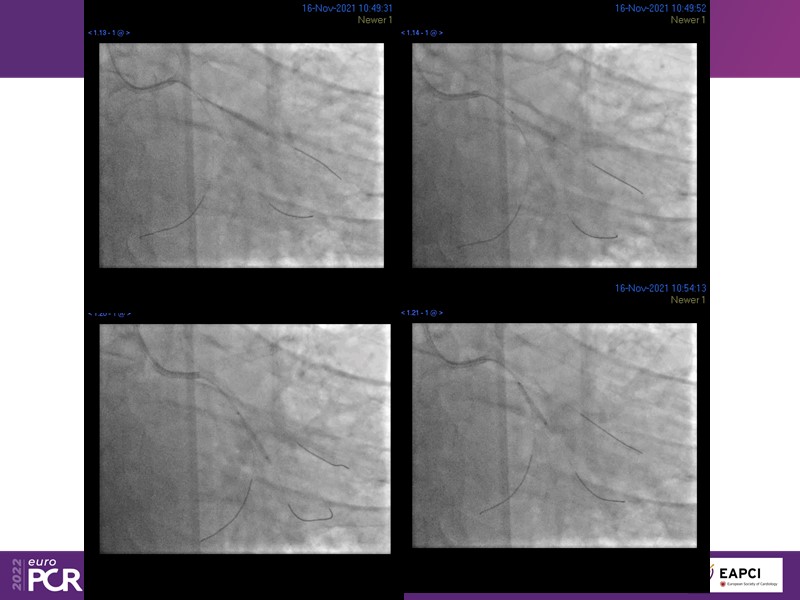

- To find out more about the application and mechanism of a sirolimus coated balloon for coronary artery disease treatment with case presentations in complex settings

- To understand how useful is a DES and DCB stent platform in complex coronary artery disease settings with case demonstrations and follow-up in diabetes mellitus